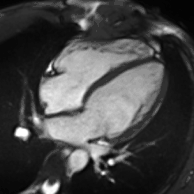

Heart function using cine imaging

Functional and structural information is acquired using bSSFP cine sequences. These are usually retrospectively-gated and have intrinsically high contrast in cardiac imaging due to the relatively high T2:T1 ratio of blood compared to myocardium. Images are typically planned sequentially to achieve the standard cardiac planes used for assessment. Turbulent flow causes dephasing and signal loss allowing valvular disease to be qualitatively appreciated. The left ventricular short axis cines are acquired from base to apex and are used for quantifying end-diastolic and end-systolic volumes, as well as myocardial mass. Tagging sequences excite a grid pattern that deforms with cardiac contraction allowing strain to be assessed.